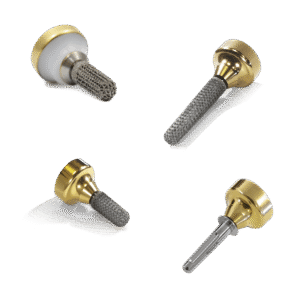

Bộ lấy gân gấp ngón tay bao gồm hai phần:

• Đầu dò và giá đỡ kim tích hợp bao gồm một dụng cụ co giãn và kéo dài với một đầu tròn nhẵn, nửa cứng ; đầu kia có tiết diện co giãn để luồn kim cong và chỉ khâu qua ống nhựa.